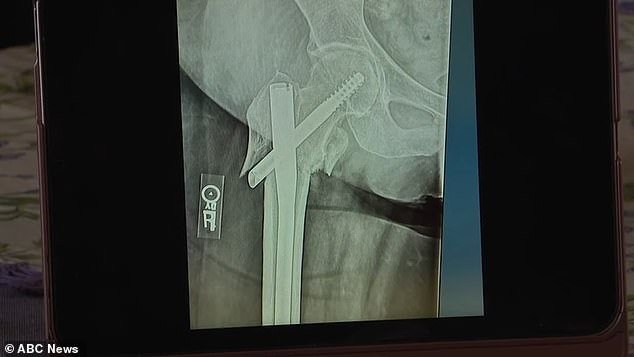

Ketika dia akhirnya tiba di rumah sakit, Kirby mengetahui seberapa parah cedera yang dialaminya - patah total pada tulang paha dengan fragmen-fragmen yang banyak.

Ia menjalani operasi pada pinggulnya dan ujung femur pada 9 Juni dan harus menghabiskan tiga minggu di rehab.